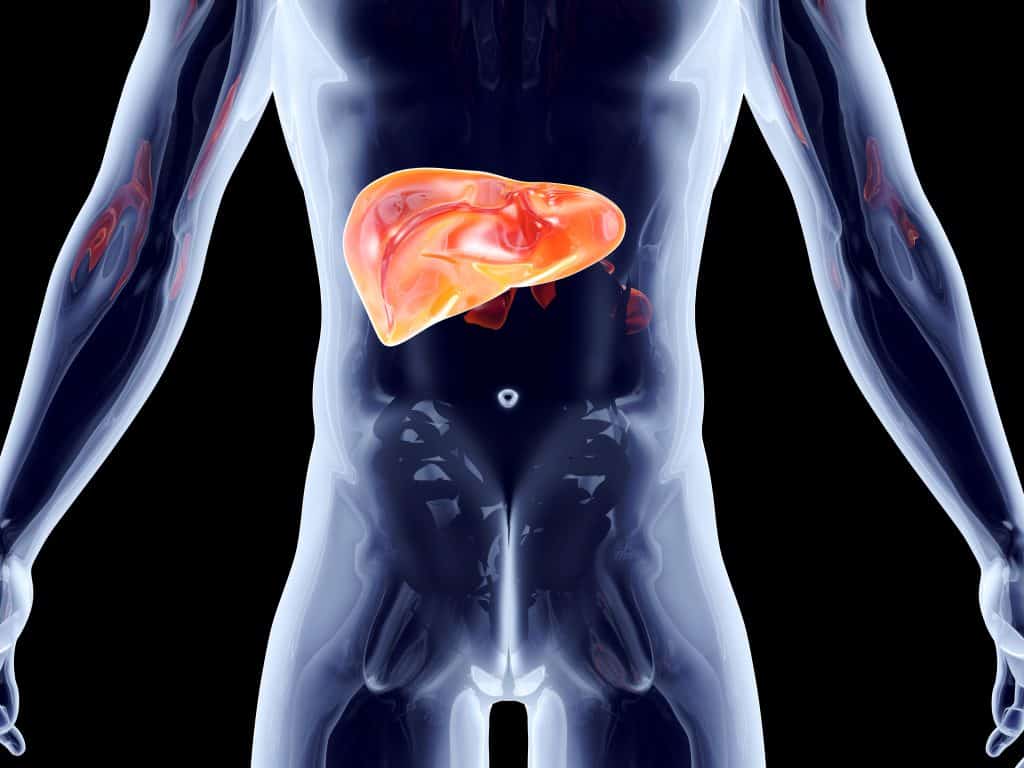

Često se držimo za želudac i izgovaramo čuvenu uzrečicu nekome tko nas uporno frustrira i nervira "ideš mi na jetra", a da se uopće ne zapitamo nakojoj strani se nalazi jetra i gdje točno. Ta neparna i najveća žlijezda u tijelu se nalazi u gornjem dijelu trbuha na desnoj strani ispod rebrenog luka. Uz to što je neparni organ, sastoji se i od dva nejednaka režnja, većeg desno, manjeg lijevo i zajedno teže oko 1,5kilograma.

Jetra ima tri strane, gornju ispupčenu, donju položenu na debelo crijevo i stražnju sraslu uz dijafragmu, a ovijena je ovojnicom koja širenjem uzrokuje bol u jetri. Režnjeve razdvaja hilus (porta) jetre kroz koji prolaze živci i krvne žile. Ispod donjeg dijela jetre se nalazi žuč iz koje žučni kanali također prolaze kroz hilus. Dvostruka opskrba jetre krvlju uključuje nutritivni (hranjive tvari i kisik za samu jetru, jedna trećina krvi) i funkcionalni krvotok jetre koji opskrbljuje ostale organe u tijelu, sa preostale dvije trećine krvi.